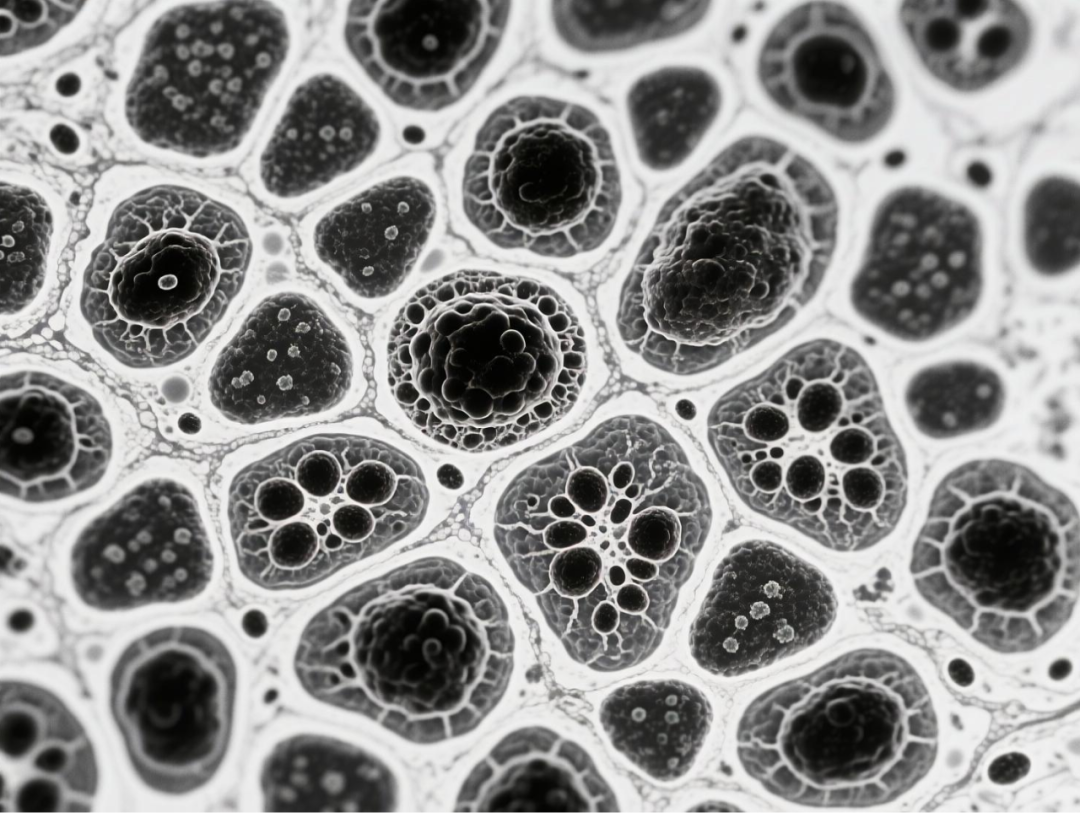

台式扫描电镜在本研究中发挥了关键的表征作用,为微气泡系统的结构验证提供了直观而精确的证据。研究团队使用泽攸科技ZEM18台式扫描电镜对冻干后的BCG-MBs进行金溅射镀膜处理后,在不同放大倍数下观察其表面形态,清晰地展示了微气泡规则的球形结构以及BCG在微气泡表面的不规则分布状态。这一表征不仅确认了微气泡制备工艺的成功,还直观揭示了BCG在微气泡中的物理分布特征,为理解药物释放机制提供了结构基础。扫描电镜图像作为重要的形态学证据,有力支持了后续对微气泡浮力特性、药物释放行为及生物效应的分析,是连接材料设计与功能验证的关键环节。